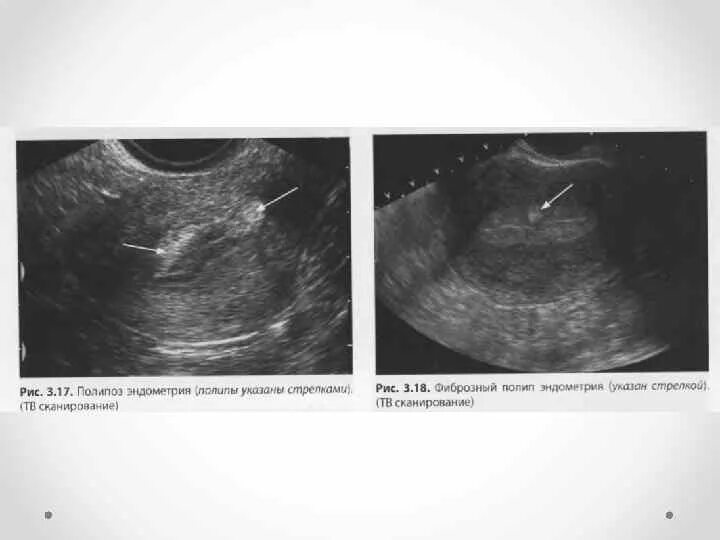

Как выглядит полип в матке на узи